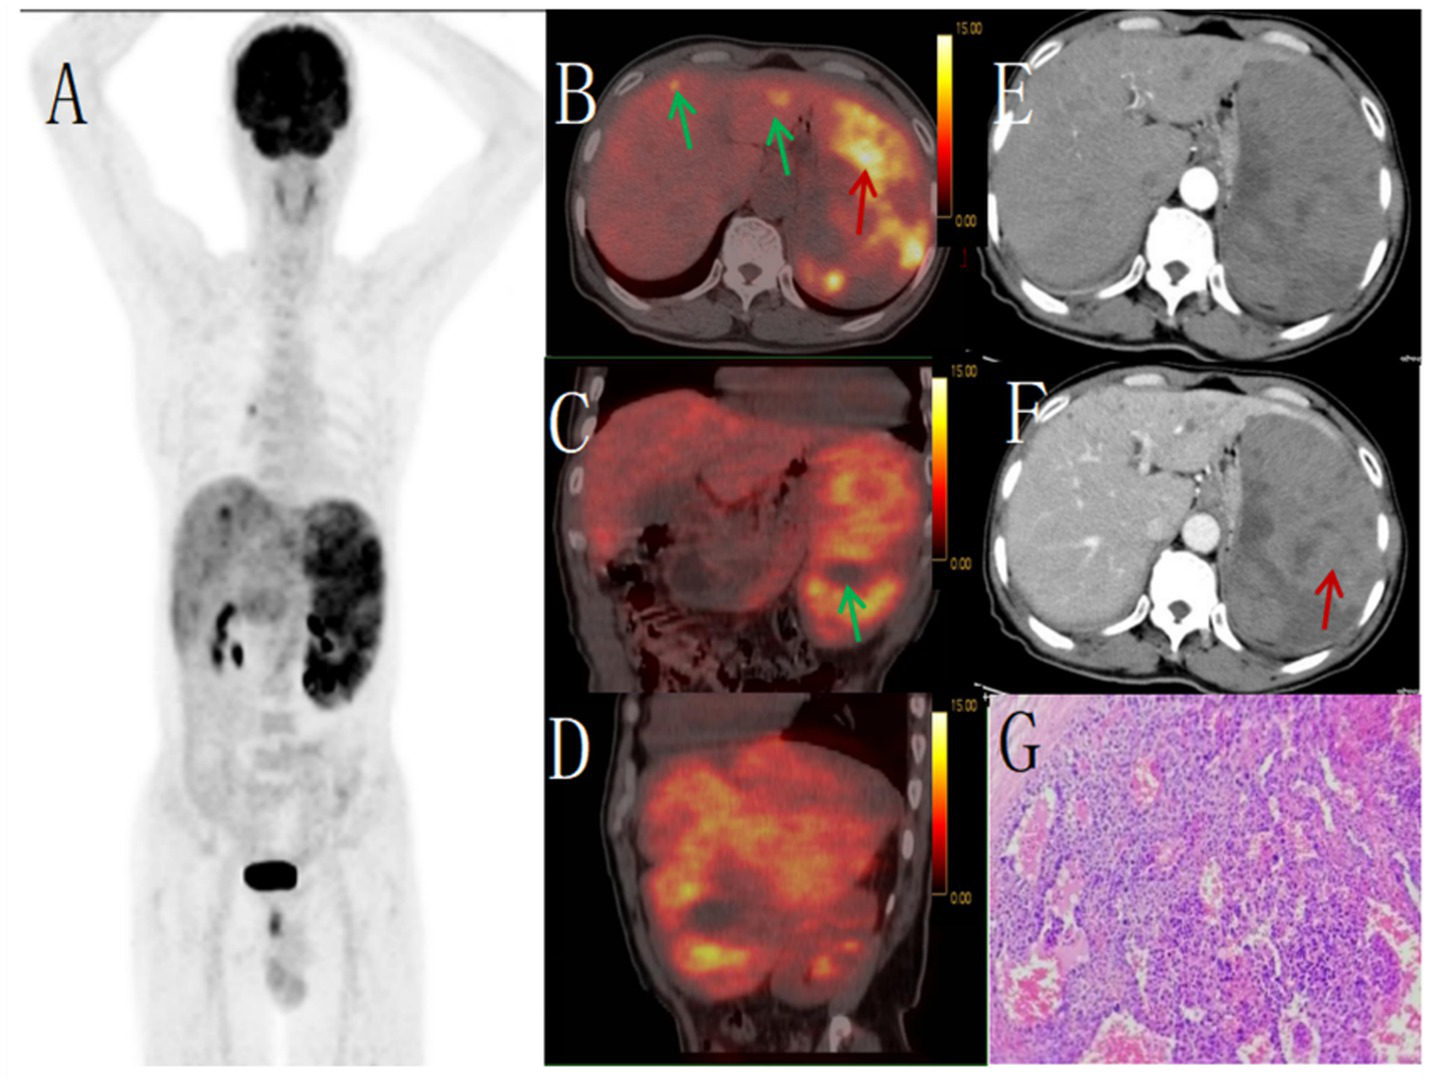

Figure 1

Female, 85 years old, diffuse large B-cell lymphoma. (A) whole body MIP, (B) axial fusion, (C) coronal fusion, (D) sagittal fusion, (E) axial CT, (F) coronal CT, (G) H-E × 200. 18F-FDG PET/CT demonstrated splenomegaly with an irregular soft tissue density mass (maximum cross-sectional dimension 17.7 × 8.5 cm) showing heterogeneous density and small hypodense necrotic areas. The lesion exhibited uniformly increased radiotracer uptake with a maximum standardized uptake value (SUVmax) of 14.4 (arrow, B–D). CT demonstrates an enlarged spleen with heterogeneous attenuation, showing multiple nodular and small patchy hypodense lesions. On contrast-enhanced scans, the spleen exhibits mild enhancement, while the necrotic areas show no significant enhancement (E). PET/CT-guided splenic biopsy confirmed the diagnosis of diffuse large B-cell lymphoma, non-germinal center subtype (G).